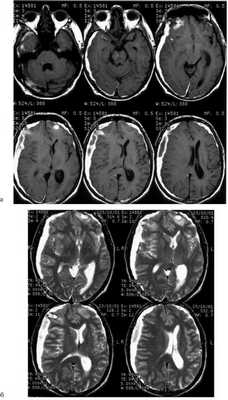

При МРТ выявлены обширная субдуральая гематома, распространяющаяся от лобной до затылочной области справа, смещение срединных структур влево на 16 мм, а также множественные каверномы головного мозга: небольшая кавернома, расположенная на конвекситальной поверхности правой лобной доли, и небольшая кавернома в полюсе левой лобной доли (рис. 1). Рис. 1. Больной П. МРТ при поступлении. Т1 (а), Т2 (б) — взвешенные изображения. Видна обширная острая субдуральная гематома справа и каверномы лобных долей: поверхностно расположенная кавернома правой лобной доли (источник кровоизлияния), кавернома полюса левой лобной доли. Смещение срединных структур влево до 16 мм. При электроэнцефалографии выявлены диффузные изменения, свидетельствующие о раздражении коры мозга. Отмечена межполушарная асимметрия за счет снижения амплитуды биопотенциалов, редукции альфа-ритма, преобладания негрубой медленной активности справа. Слева — доминирующие признаки раздражения коры с наличием негрубой эпилептиформной активности. Отмеченные изменения более выражены в височно-теменно-затылочных областях.

Послеоперационный период протекал без осложнений. В неврологическом статусе отмечен полный регресс имевшейся симптоматики. Контрольная К.Т. подтвердила тотальное удаление гематомы (рис. 2). Рис. 2. Больной П. Послеоперационная К.Т.. Гематома удалена полностью, компрессия и смещение мозга регрессировали.